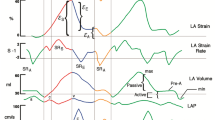

Left atrial phasic function

LA function consists of 3 phases (Fig. 1): reservoir, conduit and booster pump phases, which are responsible for the transformation of the continuous pulmonary venous return flow into intermittent LV filling [26]. During ventricular systole and isovolumetric relaxation, the LA acts as a ‘reservoir’ receiving blood flow from the pulmonary veins due to a decrease in filling pressure, leading to an increase in LA size. The conduit phase occurs during early diastole, and reflects passive emptying of the LA into the LV, governed by the transient LA to LV pressure gradient. Finally, booster pump (contraction), for those in sinus rhythm, occurs during late diastole resulting in active LA emptying attributed to the Frank-Starling mechanism, afterload and myocardial contractility [27,28,29].

Similar strain curves are generated by both TTE and CMR techniques (Fig. 2G). LAS/LASR can be measured for the three LA phases [61]: reservoir function (LAS_r and LASR_r), conduit function (LAS_cd and LASR_cd) and contraction booster-pump ( LAS_bp and LASR_bp). LAS_cd can be calculated as: LAS_cd = LAS_r – LAS_bp.

Overall, LAEF values are lower on CMR compared to TTE, but LAS values seem to be closer together (Fig. 3). The variation in values caused by vendors and imaging modality however, raises important questions regarding the validity and generalisability of the technique. Reference ranges require further validation by studying larger cohorts, and considerations of the possible influence of field strength and vendors. LASR by STE and both LAS and LASR by FT-CMR have no standardised reference ranges to date due to limited published literature on normal ranges and the variability mentioned above.

Normal values of LA phasic function by strain analysis. Table illustrates normal ranges by TTE vs CMR for: LAS_r = LA strain at reservoir, LAS_cd = LA strain at conduit, LAS_bp = LA strain at booster-pump phase. Normal ranges from[64, 68, 105, 106]. The graph illustrates the change in LA strain during the cardiac cycle